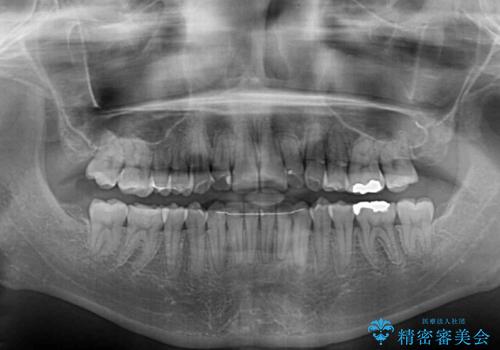

- 顕著な八重歯など、上下前歯のデコボコとスペースを気にして来院された患者様です。

八重歯改善には第一小臼歯の抜歯が必要であり、移動量が多いことから補助装置により八重歯を引き込むこととしました。

インビザラインでの治療をご希望であったので、インビザラインにて行うこととしましたが、右側前歯の改善にはワイヤー矯正が必要となる可能性があることをお伝えした上で治療を開始しました。

補助装置だけでなく、部分的にワイヤー矯正も使用しましたが、上下のスペースは改善しきれず、側切歯(前から2番目の歯)や顕著な八重歯は、インビザラインで治療するには限界があることがよく分かりました。